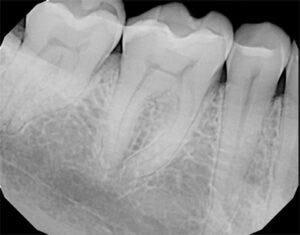

Walking in I thought I’d be lucky if it was maybe a root canal and no major dental surgery. The cleaning was unremarkable and the x-rays showed that I had two fillings to fix and that was it. I was shocked. I wanted to ask the dentist if he was sure. All the sweet tea and cigarettes I had consumed in the past year alone, no throat cancer or anything? It wasn’t disappointment, it was just, huh, I guess things aren’t that bad. I mean, my family heirlooms were still stolen from my place when it was vandalized and I had to install security cameras, but my health was still above 80%.